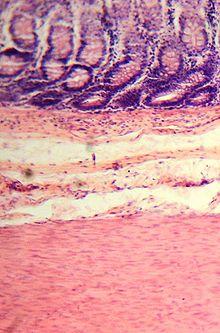

Histological section.

The wall of the large intestine is lined with simple columnar epithelium with invaginations. The invaginations are called the intestinal glands or colonic crypts.